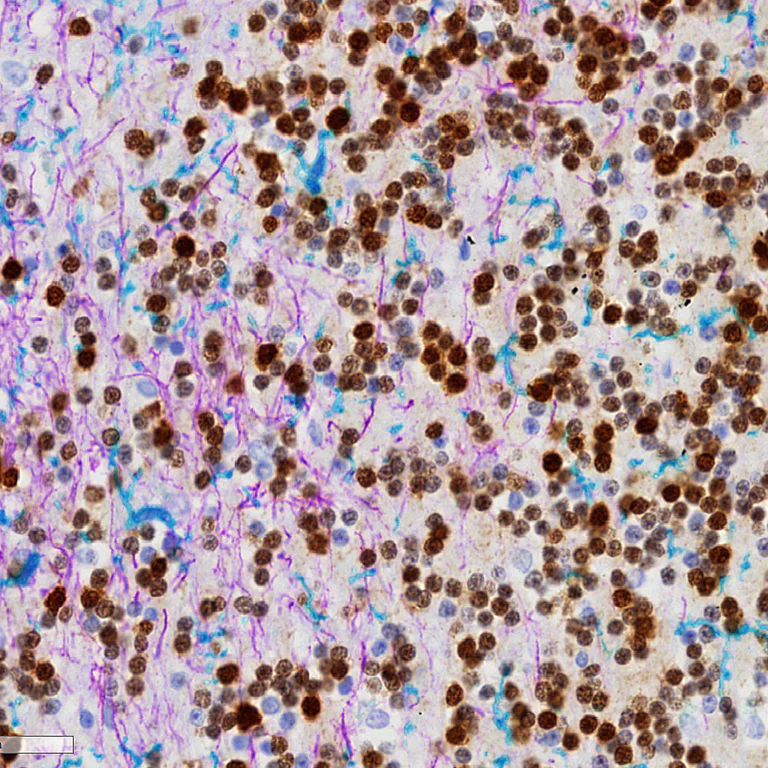

Multiplex immunohistochemistry - Anti-Iba1 antibody [EPR16588] - Microglia marker (AB178846)

Chromogenic multiplex immunohistochemical staining of FFPE normal human cerebellum tissue. ab177487, anti-NeuN DAB chromogen. ab68428, anti-GFAP purple chromogen and ab178846, anti- Iba1 teal chromogen plus haematoxylin counterstain. Chromogenic immunostaining was performed on a Roche Ventana Discovery Ultra instrument. The section was deparaffinised and incubated with CC1 solution for 24min 100°C. Following this with 3 rounds of staining in the order of ab177487 (1/600), ab178846 (1/4000) ab68428 (1/1000). Between rounds of staining, antibody denaturation was conducted using Ultra CC2 solution for 8min at 100°C to avoid cross reactivity. Signal was developed with anti-rabbit HQ followed by anti-HQ HRP coupled with Chromomap DAB kit, Discovery purple or Discovery teal chromogens and haematoxylin II counterstain.